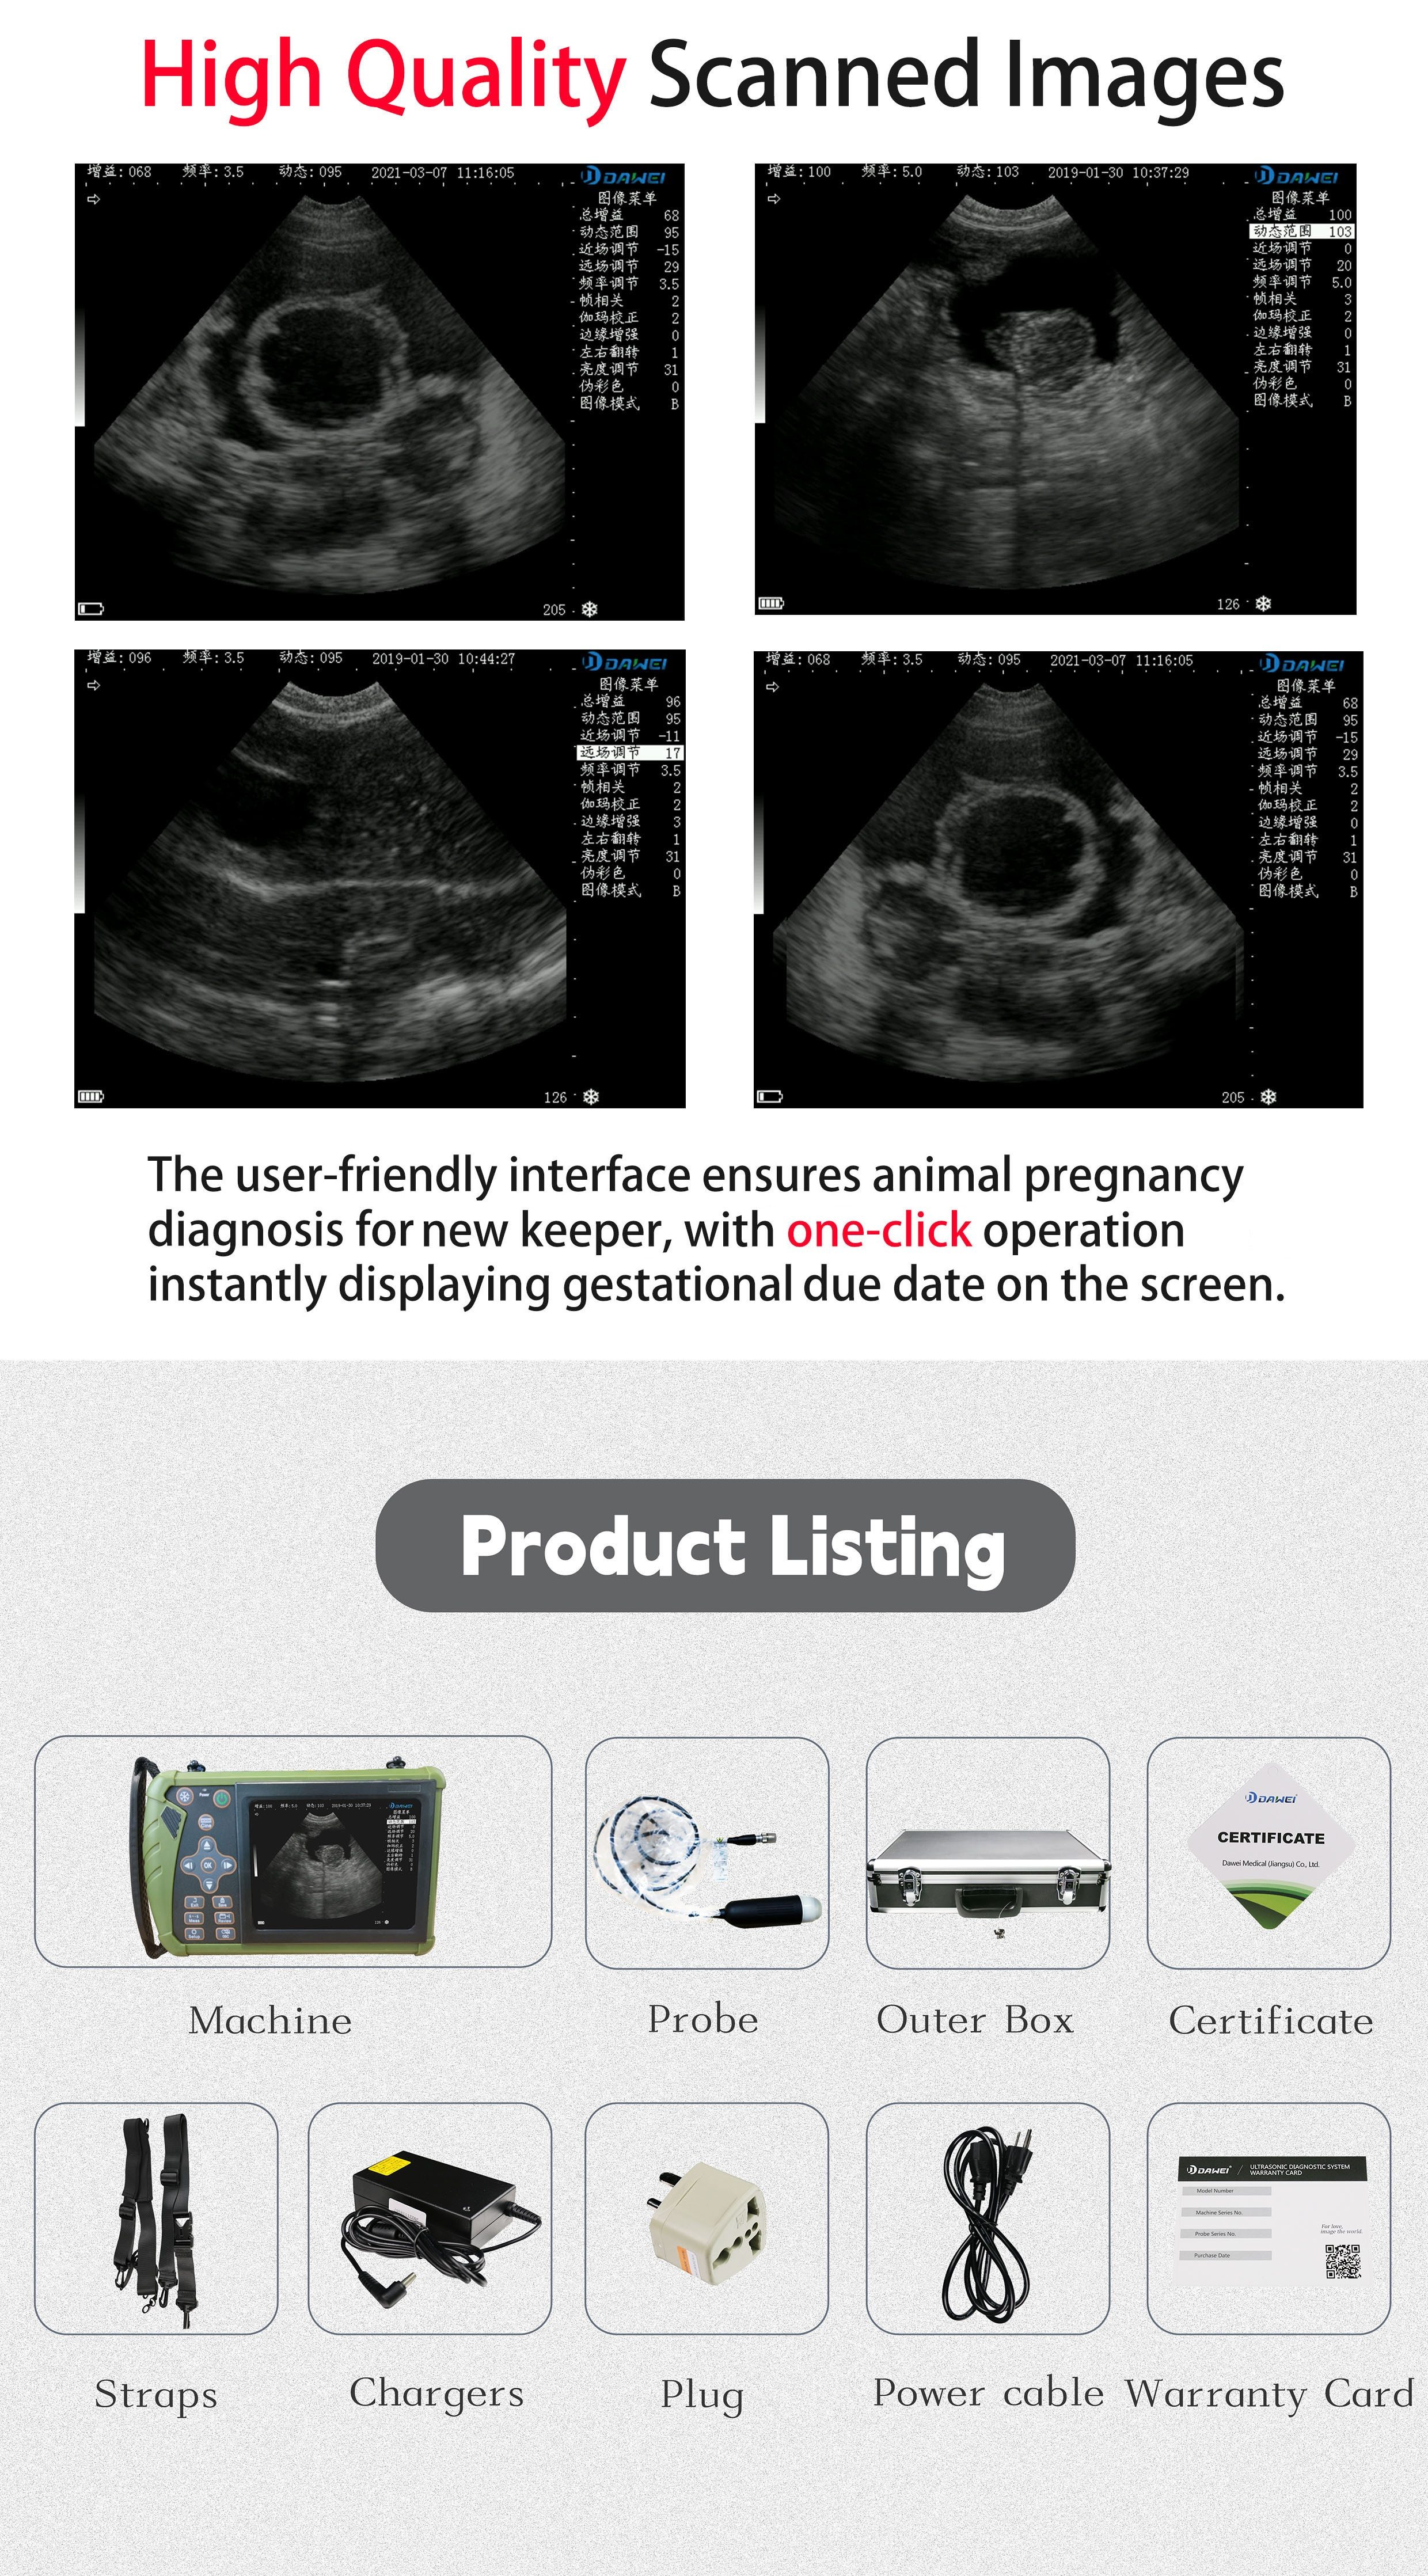

3.5MHz Probe: Ideal For Ultrasound Imaging And Pregnancy Testing Of Medium-sized Animals Such As Pigs, Sheep, Dogs, Etc

DAWEI-S0 Is A Portable Veterinary Ultrasound (B-ultrasound) Diagnostic Instrument. Its Superior Product Performance And Ergonomic Handheld Design Bring More Convenience To Users During Testing.